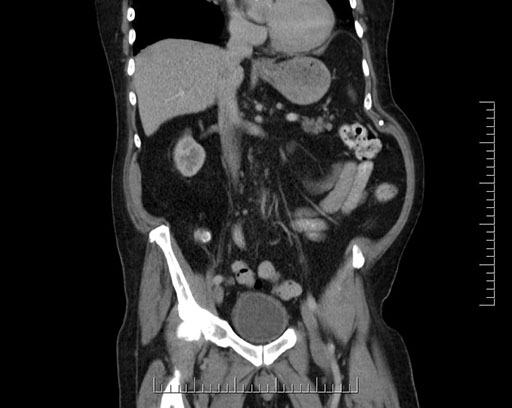

Coronal - stented